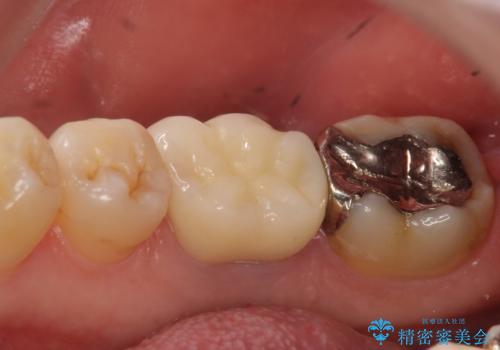

再根管治療を行い、フィステル(膿の出口)の消失および根尖病変の縮小を確認後、オールセラミッククラウンによる補綴を行いました。

今回用いたオールセラミッククラウンはジルコニアフレームという白い素材の上にセラミックを盛っているため、審美性が非常に高いのが特徴です。

また、ジルコニアは人工ダイヤモンドの材料にも使われているほど高い強度を持っており、そのためオールセラミッククラウンは審美性だけでなく、奥歯やブリッジの補綴も可能とするクラウンです。